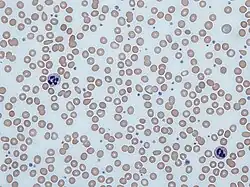

Platelet storage pool deficiency is a family of clotting disorders characterized by deficient granules in platelets. Individuals with these disorders have too few or abnormally functioning alpha granules, delta granules, or both alpha and delta granules and are therefore unable to form effective clots, which leads to prolonged bleeding.[3][4] Platelet storage pool deficiency can be acquired or inherited.[3]